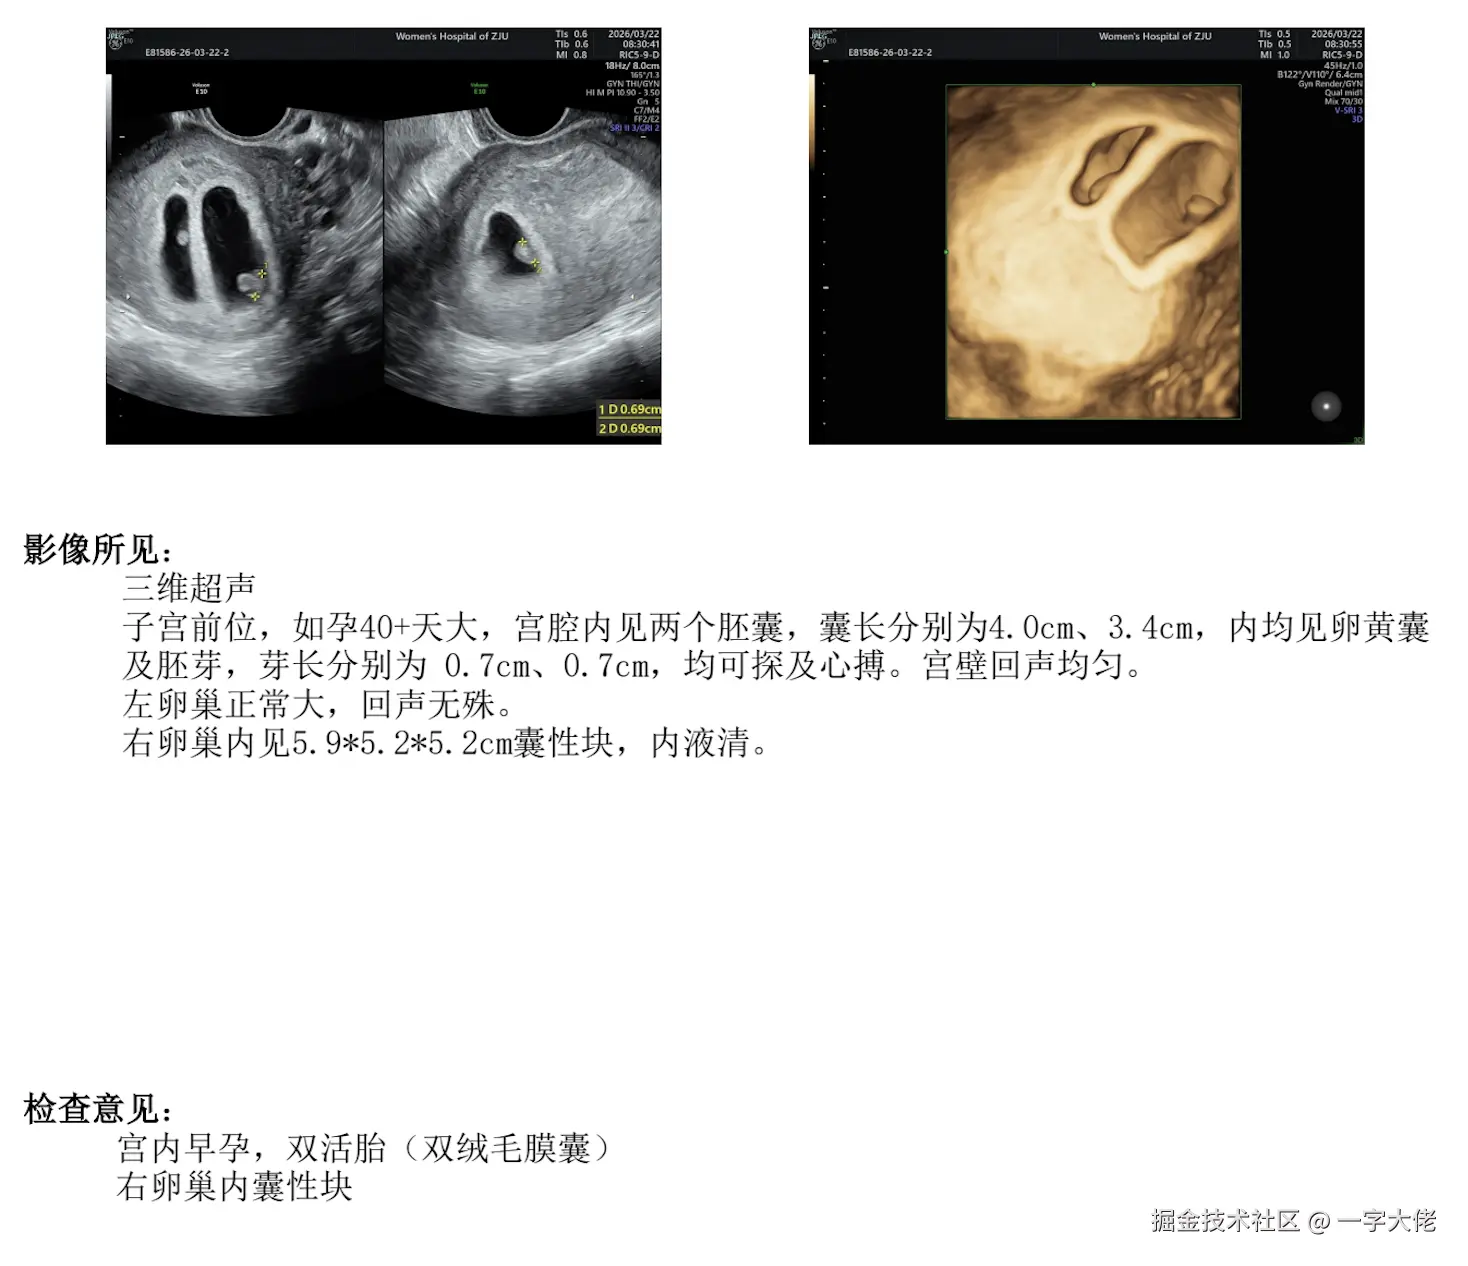

jym,又紧张又焦虑又开心。我滴老天爷。

一字大佬于2026-03-24 10:02发布的图片